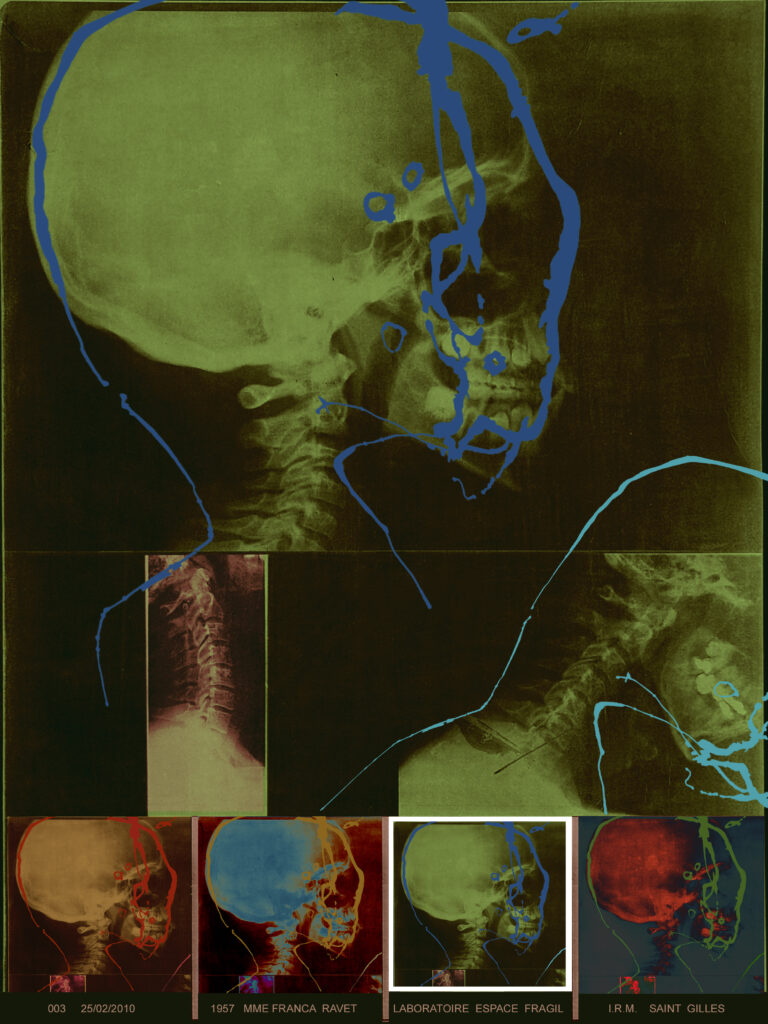

L’artiste est partie d’une empreinte graphique donnée qu’elle assimile à “une sorte d’IRM cérébral”, répétée de manière obsessionnelle et répétitive.

Du point de vue du sens, Ravet restitue ce processus de “conception, de transmission et d’effacement des informations mémorisées tout au long de nos vies”.

En livrant également des grands formats “diasec” sur plexiglas, elle impose un traitement numérique à sa peinture. C’est alors forcément toute la question du fichage et du stockage des données informatiques qui apparaît.